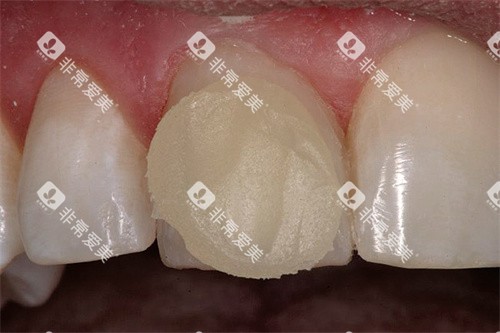

• 基础修复:烤瓷牙冠500元起,经济实用;全瓷牙冠1500元起,美观自然且生物相容性好;

• 美学修复:牙齿贴面1800元起,适用于改善前牙形态或轻度变色问题。